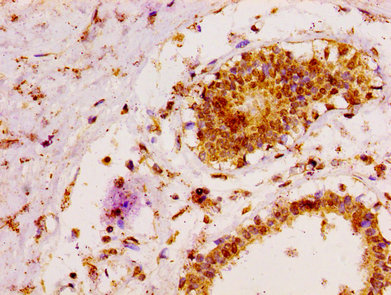

IHC image of CSB-PA013428LA01HU diluted at 1:100 and staining in paraffin-embedded human breast cancer performed on a Leica BondTM system. After dewaxing and hydration, antigen retrieval was mediated by high pressure in a citrate buffer (pH 6.0). Section was blocked with 10% normal goat serum 30min at RT. Then primary antibody (1% BSA) was incubated at 4°C overnight. The primary is detected by a biotinylated secondary antibody and visualized using an HRP conjugated SP system.